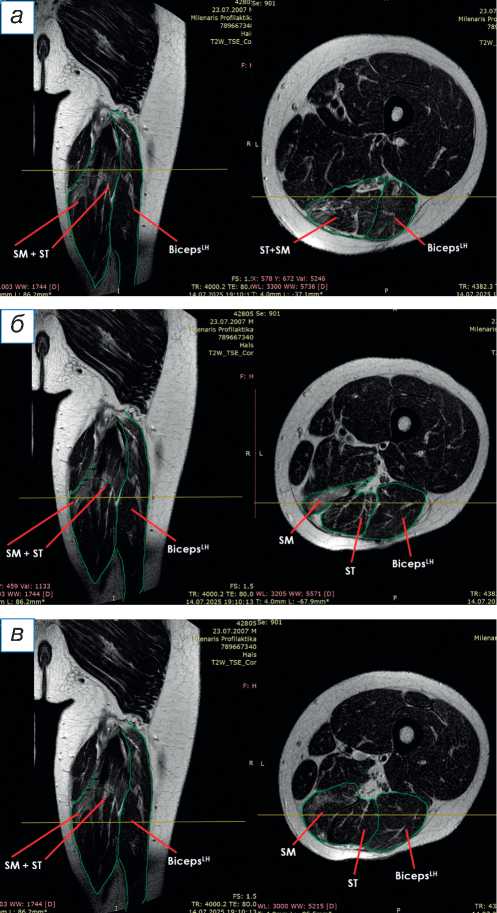

При поступлении в центр пациенту выполнены лучевые методы исследования нижних конечностей, в частности панорамная рентгенография и компьютерная томография (КТ) нижних конечностей; сравнительная МРТ мягких тканей правого и левого бедра (рис. 2). По данным рентгенографии и КТ-исследования, костно-суставной патологии не обнаружено. По результатам МРТ определены повреждения всех трёх мышц различной степени тяжести — SM, ST, BicepsLH (расположены в порядке убывания; см. рис. 2, а ). Длинная головка двуглавой и полусухожильная мышцы, вероятно, были оторваны у места крепления и не подверглись значительной ретракции; начало брюшка полуперепон-чатой мышцы визуализировано на границе верхней и средней трети бедра (ретракция 9 см).

Рис. 2. Сравнительная магнитно-резонансная томография мягких тканей правого и левого бедра (аксиальные и фронтальные срезы): а — изменение нормальной архитектоники полусухожильной, полуперепончатой и длинной головки двуглавой мышцы на уровне верхней трети правого бедра; б — на данном уровне не прослеживается мышечное брюшко полуперепончатой мышцы; в — на границе верхней и средней трети прослеживается мышечное брюшко полуперепончатой мышцы, спаянное с большой приводящей; определяется разница по форме и диаметру поперечника полусухожильной мышцы; г — на уровне средней трети отчётливо проявляются мышечное брюшко полусухожильной мышцы, несоответствие поперечного диаметра полуперепончатой и полусухожильной мышц с контралатеральной стороной, гипертрофия короткой и длинной головки бицепса; д — аналогичная картина и на границе средней и нижней трети. ST ( m. semitendinosus ) — полусухожильная мышца; SM ( m. semimembranosus ) — полуперепончатая мышца; BicepsLH ( m. biceps femoris ) — длинная головка двуглавой мышцы.